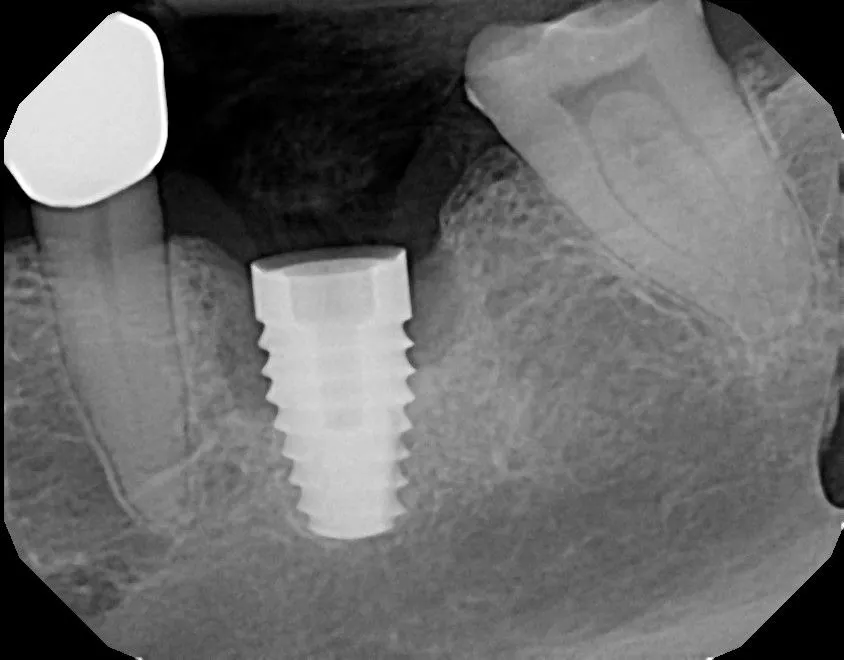

after